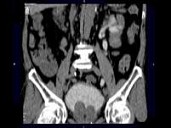

男,72岁,排尿困难1年余,无手术病史,CT扫描如图所示,下列说法正确的是?(?)

• A.一侧肾脏缺如

• B.膀胱的后上方可见一囊性肿物,该囊性肿物与膀胱相通

• C.考虑为先天性孤立肾

• D.该囊性肿物考虑为膀胱憩室

• E.该囊性肿物考虑为输尿管囊肿